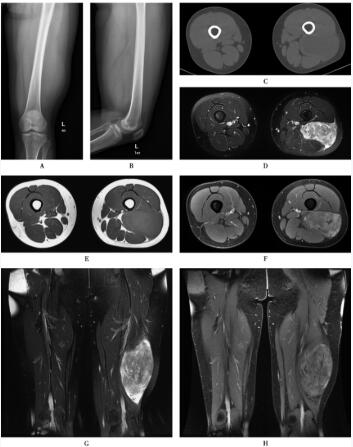

影像学检查表现见图1。

图1黏液纤维肉瘤

MRI表现:软组织内类圆形或分叶状肿块,T1WI呈等、稍高信号,T2WI呈等、高信号。增强扫描肿瘤中度或显著不均匀强化,还可清楚显示毗邻血管神经束的包绕情况。

2.X线表现为软组织肿块,少有钙化,可能有邻近骨质的侵蚀破坏。

3.CT表现示软组织内团块状或不规则等密度、高密度肿块,肿瘤内常有坏死、囊变,少有钙化。

本肿瘤组织成分复杂,病灶在MRI的信号多不均匀,平扫T1WI呈等或稍低信号,T2WI呈稍高信号,其内部有点状或片状显著高信号区为坏死或间质黏液样变性。当病灶内含胶原纤维较多时,在T2WI上可表现为稍低信号。增强扫描肿瘤显著强化,提示为富血供肿瘤。